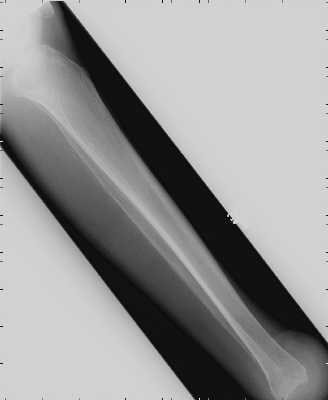

and thus non-cosmetically pleasing prosthesis. The level of

the amputation in generally at the distal tibia and fibula 0.6cm proximal to the periphery

of the ankle joint and passing through the dome of the ankle centrally. In the past,